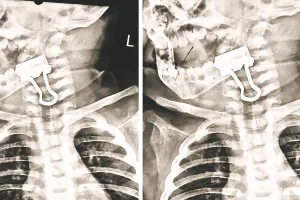

Read More... हलक में अटकी क्लिप : एक साल के मासूम की सांसें अटकी, डॉक्टर ने तीसरे प्रयास में पेपर बाइंडिंग क्लिप निकाल बचाई जान

एक साल के मासूम ने पेपर बाइंडिंग क्लिप निगल लिया, जिससे उसे सांस लेने में दिक्कत होने लगी। ऐसे में परिजन बच्चे को लेकर बांगड़ अस्पताल के ईएनटी विभाग पहुंचे। डॉ. कटारिया ने बताया कि क्लिप सांस नली के मुहाने में जाकर अटक गया था।